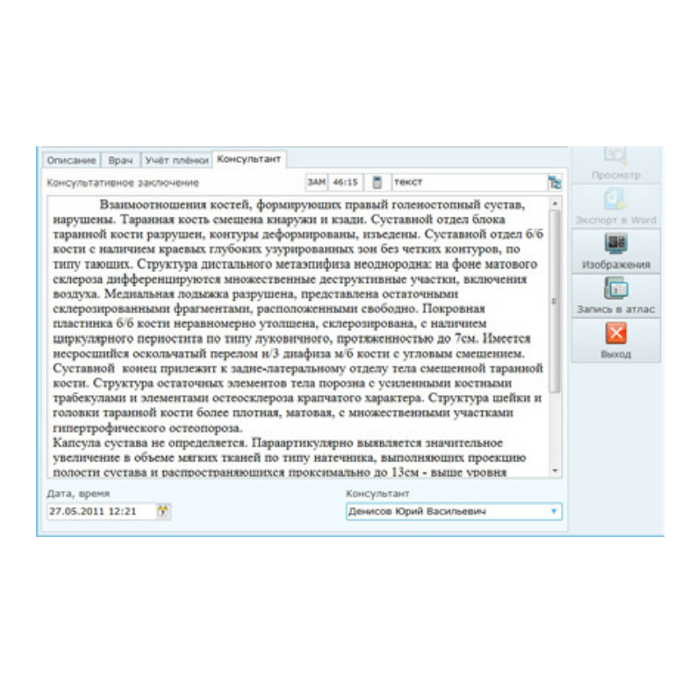

- Описание и отчетность: Удобные рабочие станции для врачей-рентгенологов с шаблонами протоколов, голосовым вводом и поддержкой нормативных форм.

- Телемедицинские консультации: Встроенные возможности для удаленных консилиумов и получения вторых мнений от профильных специалистов.